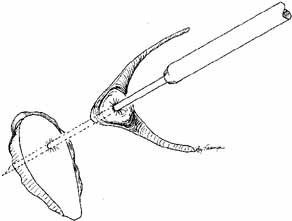

Fig. 56 Open bypass tube method. A. Surgery is the same as for a routine dacryocystorhinostomy (DCR) until

the formation of mucosal flaps. B. A portion of the caruncle can be excised to provide more room for the

Jones tube collar. The needle is removed, and the Jones tube inserted

over a straight probe. C. A 6–0 nonabsorbable suture is tied around the collar to the lid

on the palpebral surface. Fig. 56 Open bypass tube method. A. Surgery is the same as for a routine dacryocystorhinostomy (DCR) until

the formation of mucosal flaps. B. A portion of the caruncle can be excised to provide more room for the

Jones tube collar. The needle is removed, and the Jones tube inserted

over a straight probe. C. A 6–0 nonabsorbable suture is tied around the collar to the lid

on the palpebral surface.